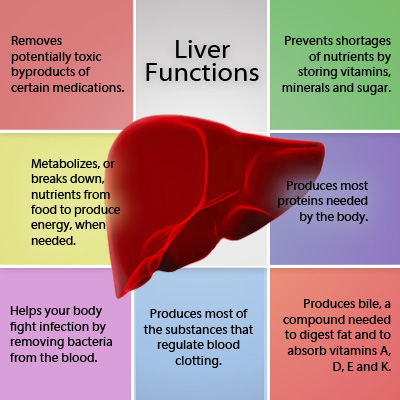

7. The Excretory System (human)

- Excretory organs and their functions e.g. kidney, skin and lungs.

- The process of excretion.

- Waste materials of excretion e.g. carbon (iv) oxide, sweat and urine.

- Need for excretion.